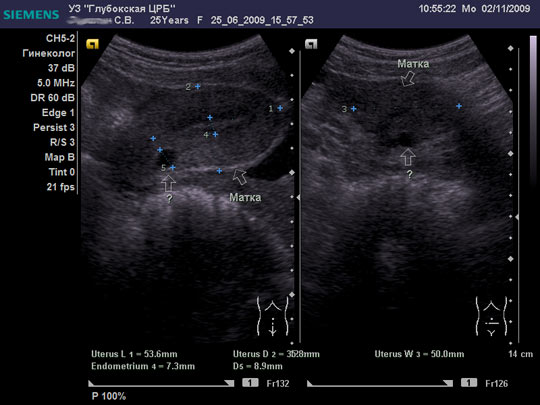

Женщина 25 лет предъявляет жалобы на периодически возникающую болезненность в нижних отделах живота, боли появились около 6-8 мес. Менструальная функция не нарушена. В анамнезе кесарево сечение, ребёнку 2,5 года.

Я тоже думал про наботовы желёзки, но меня смутил тот момент, что не явилось ли это образование следствием оперированной матки, лигатуры... ну чего-то там с ними... или что-то в этом духе????

Согласен, Наботова или эндо-цервикальная киста шейки. Ничего специфического.

Naboti пишем, эндометриоз в уме

запросто. об эндометриозе надо думать, когда ov.nabotae несколько. и к тому же присутствуют гиперэхогенные линейные включенияDoc писал(а):Спасибо.